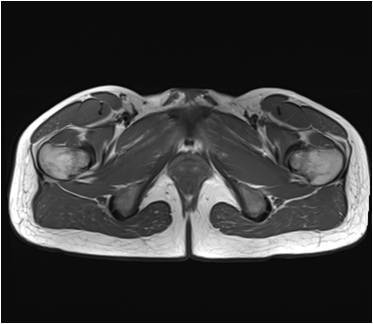

Gallery of Unlabled Radiographs from Lecture (Dr. French) - 2020

Click a thumbnail to enter the gallery display. Click the file name link at the bottom left of the gallery display to view the image at high resolution.

Labeled Plates from Lecture (Dr. French) - 2020

RadiologyLowerLimbThoraxQuestionPoolLabeled_01_2020.pdf

Click right side of plate to step forward or left side of plate to step backward.